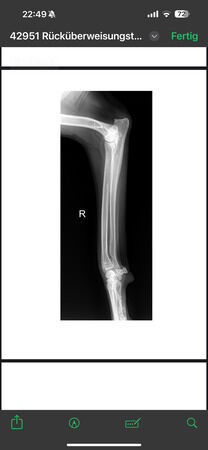

radiologisch kein Kniegelenkserguß oder Arthrose, nur Weichteilschwellung im Bereich distaler

Patellasehne, Elle proximal verdickt und Fehlstellung (alte, verheilte Fraktur?), keine deutlich

Ellbogenarthrose, leichtgradige Fehlstellung Unterarm li., auch leichtgradige Fehlstellung Radius re.

Alle Gelenke sonst ohne deutliche Arthrosezeichen.